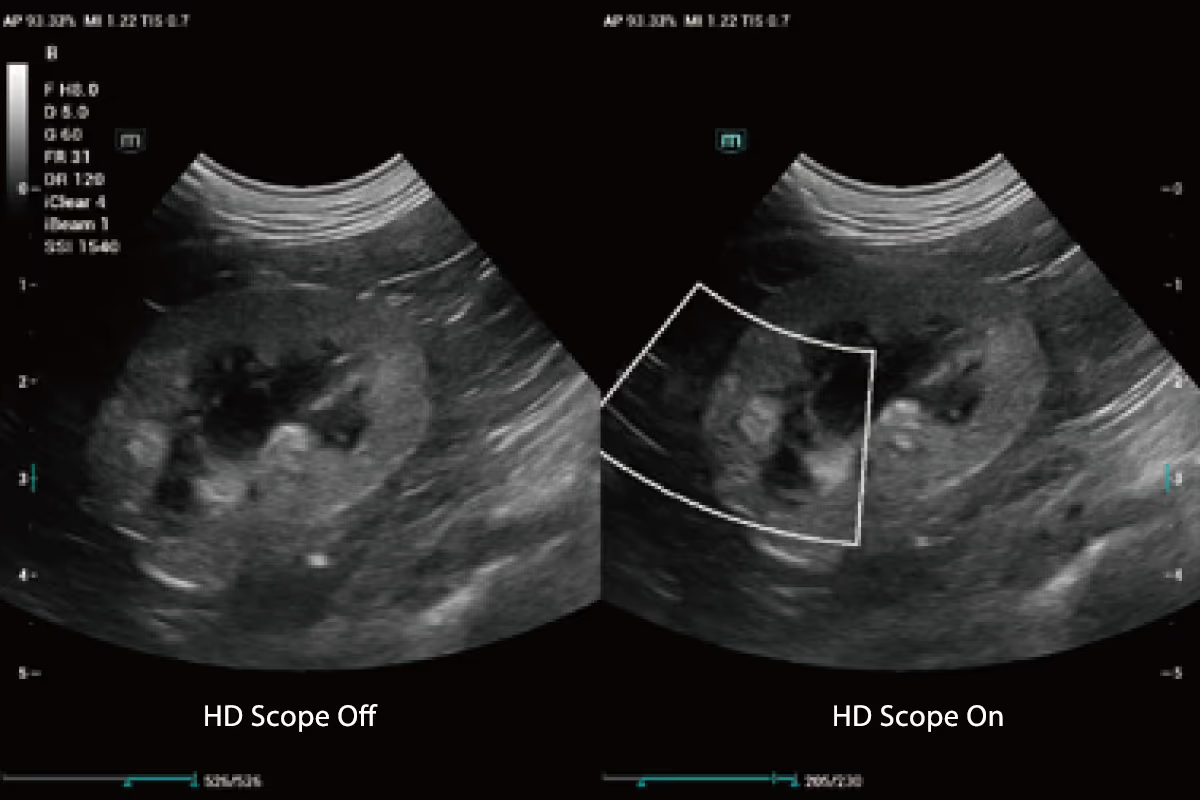

HD Scope, yeni nesil platform tarafından toplanan kanal verilerini işleyerek belirli bir alandaki detay bilgilerini ve görüntü kontrastını iyileştirebilir.

Lezyonun sınırını çevreleyin ve doğru bir ölçüm elde edin.